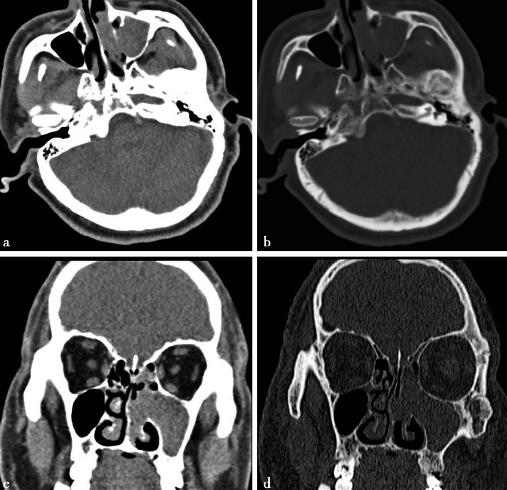

病例2-2-1:以耳部为中心的头颅CT扫描及重建图像。

图1a,轴位软组织窗。图1b,轴位骨窗。图1c,重建后冠状位软组织窗。图d,重建后冠状位骨窗。左侧上颌窦内可见实性病灶,CT值约为44HU,上颌窦口扩大,病灶凸向左侧鼻腔内,鼻中隔略向右侧偏曲,骨质受压变薄